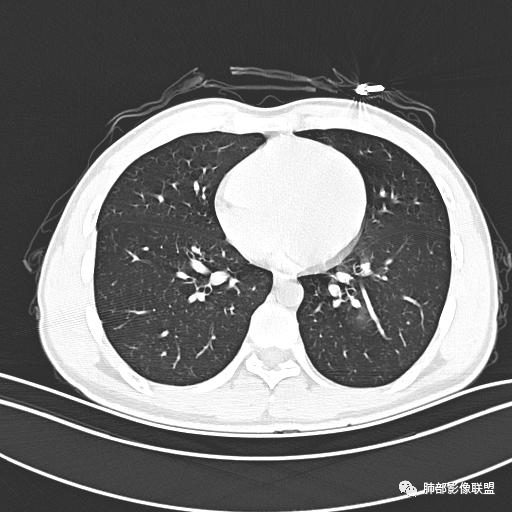

小强:青年,发热,皮疹;双肺散在结节,周围磨玻璃,点晕征,疱疹病毒感染,鉴别荚膜组织胞浆菌,结核。 大雄:青年,急性起病,发热伴全身皮疹2天,抗病毒治疗体温有下降。双肺随机分布大小不等类圆结节,“点晕征”。考虑水痘-疱疹病毒(VZV)血播询问接触史,查体皮疹分布以及形态基本可诊断。 王开金江津中心医院呼吸科:青年男性,起病急,病程短,以发热,皮疹为首发症状,感染指标以单核细胞升高为主,胸部ct双肺多发结界,周围有晕,点晕表现,随机分布,同意於老师意见,水痘疱疹病毒血流感染累及肺。 王秀仙:双肺多发大小不等结节,周围有晕,边缘模糊,呈点晕征表现。青年,急性起病,发热伴全身皮疹2天,抗病毒治疗体温有下降。考虑疱疹病毒。鉴别荚膜组织胞浆菌。 傅昌瑜:19岁男性,发热、全身皮疹2天,单核细胞增高,双肺多发结节,结节边缘见边界不清磨玻璃影。点晕征+发热、全身皮疹+单核细胞增高——考虑水痘-带状疱疹病毒肺炎。 一切∮随缘:年轻男性,发热,皮疹两天,实验室,CRP,PCT增高,影像:双肺多发散在磨玻璃结节,边界欠清,大小不等,呈点晕征改变,以血管束周围分布为主,局部血管束略增粗,其它无明显改变,考虑:1:病毒性肺炎(水痘疱疹病毒?不知道皮肤有无改变)2:真菌(组织胞浆菌,血管侵袭性肺曲霉)3:GPA4:寄生虫(实验室没有看到嗜酸细胞增高) 赵山河:双肺散在结节,周围有晕,边缘模糊,呈点晕征表现。青年,急性起病,发热伴全身皮疹2天,抗病毒治疗体温有下降。考虑水痘—疱疹病毒感染。洪桥爱:青年男性,发热、皮疹2天,伴瘙痒,皮疹于面部首发,之后进展至全身,虽然没有对皮疹进行描述,但是从出疹时间及皮疹进展情况,伴瘙痒,应该就是个水痘患者;CT提示双肺随机分布结节影,部分结节伴有边界不清晕征,考虑水痘血播肺。 刘强:年轻男性,急性起病,皮疹,发热,抗感染治疗体温下降,说明有效。影像表现为散在点晕征,感染类疾病谱(疱疹病毒,真菌,结核),结合年龄,皮肤皮疹,考虑水痘-疱疹病毒性肺炎。 小兜:男性,19岁,发热皮疹两天,颜面部至全身,CRP,降钙素及单核增高。CT示双肺散在小结节,周围伴磨玻璃影,点晕征,考虑为水痘-带状疱疹病毒(varicella-zoster virus,VZV)肺炎 必有路:青年,皮疹+发热+“点晕征”→水痘-疱疹病毒(VZV) 许慧良:青年男性患者,发热、皮疹2天,体温最高38.5℃,第3天皮疹扩展至全身,伴瘙痒,胸部CT:双肺多发随机分布的小结节,结节周边见边界模糊的晕征,考虑水痘病毒感染流心明智:男,19,急性起病,发热伴全身皮疹2天。出疹顺序头→全身,抗病毒有效。胸部CT:两肺多发大小不等类圆形实性小结节影,随机分布,结节周围环绕GGO,边界模糊,呈点晕征。出疹特点是关键,未提示。考虑:血播病毒性肺炎,水痘-疱疹病毒?麻疹?鉴别荚膜组织胞浆菌、TB、血管炎、寄生虫等。 浪迹天涯:病灶多为5-10mm大小结节,结节周围可见磨玻璃样的晕环,常多发,可分布于肺内任何区域,考虑水痘—带状疱疹病肺炎如果短时间内有新的一个区域浸润,更加能说明,